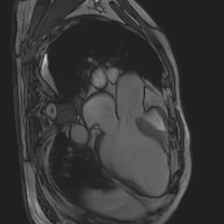

Accurate segmentation and motion estimation of myocardium have always been important in clinic field, which essentially contribute to the downstream diagnosis. However, existing methods cannot always guarantee the shape integrity for myocardium segmentation. In addition, motion estimation requires point correspondence on the myocardium region across different frames. In this paper, we propose a novel end-to-end deep statistic shape model to focus on myocardium segmentation with both shape integrity and boundary correspondence preserving. Specifically, myocardium shapes are represented by a fixed number of points, whose variations are extracted by Principal Component Analysis (PCA). Deep neural network is used to predict the transformation parameters (both affine and deformation), which are then used to warp the mean point cloud to the image domain. Furthermore, a differentiable rendering layer is introduced to incorporate mask supervision into the framework to learn more accurate point clouds. In this way, the proposed method is able to consistently produce anatomically reasonable segmentation mask without post processing. Additionally, the predicted point cloud guarantees boundary correspondence for sequential images, which contributes to the downstream tasks, such as the motion estimation of myocardium. We conduct several experiments to demonstrate the effectiveness of the proposed method on several benchmark datasets.